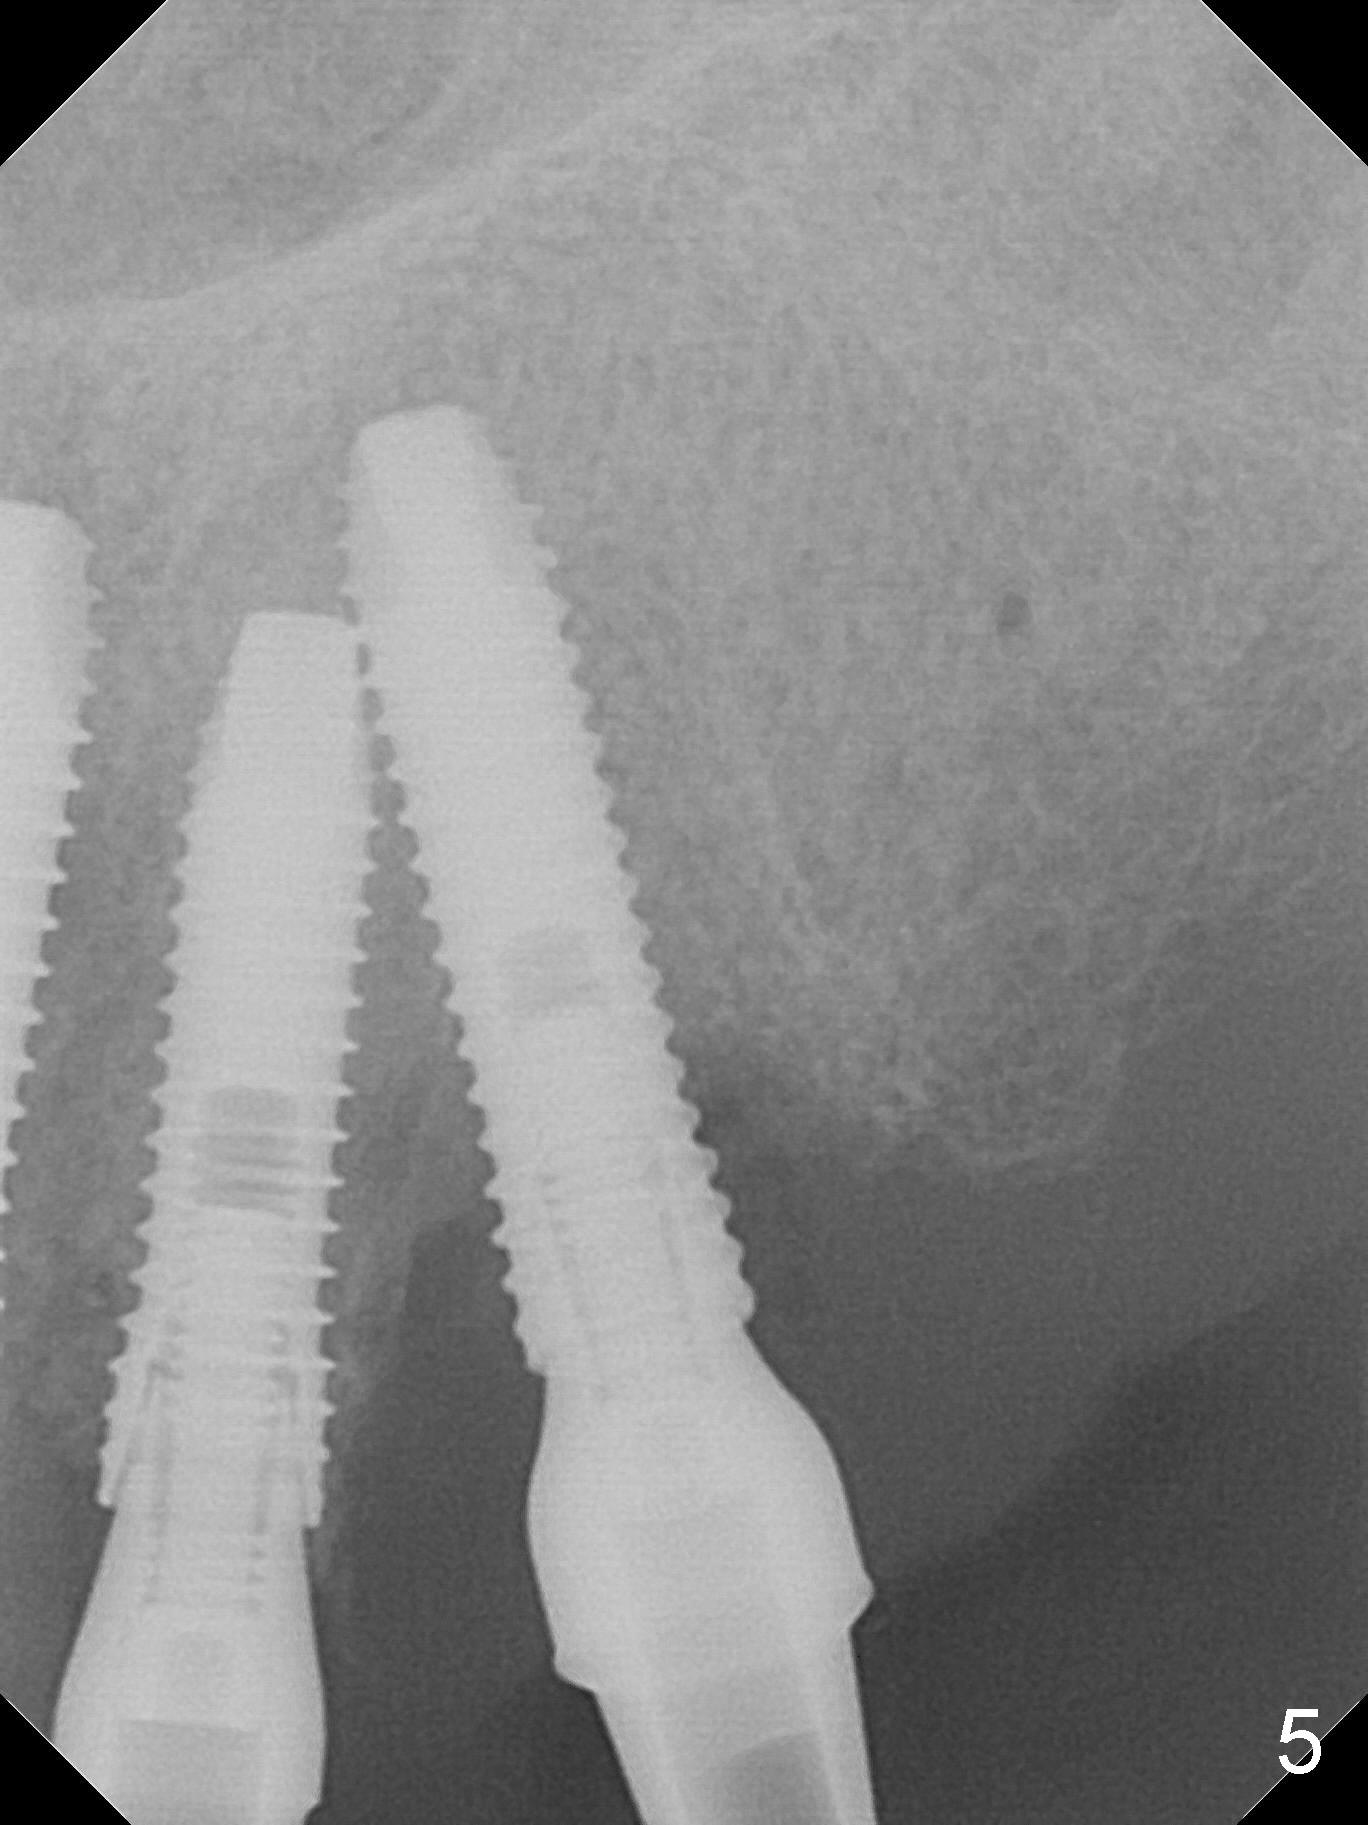

The dentition is poor except #6 and 8 (Fig.1). The gingiva is erythematous at #9-11 (Fig.2). The teeth #9 and 10 are extracted first; a 4x16 mm UF implant is placed at #9, while a 2 mm pilot drill is at the site of #10 (Fig.3). The implant at #9 is placed deeper with placement of 4.5x5.5(5) mm abutment; a 3.8x15 mm implant is placed at #10 initially (Fig.4). While the latter is placed deeper, a 4x16 mm implant is placed at #11 (Fig.5 after removal of #11-15 FPD (fixed partial denture)). In fact the trajectory at #11 is not difficult to be changed with 2 mm drill (Fig.6). After use of 3 mm drill, the implant is reinserted at #11 with ideal trajectory (Fig.7). After further seating of the implant at #11, graft is placed in the remaining sockets of #9-11 (Fig.8 *; later more graft is placed mesial to #11 implant (^)). Finally, a 4.5x7(5), 4.5x15° B (4) and 5.5x7(5) mm abutments are tightened and prepared (Fig.9) for splinted provisional at #9-10.